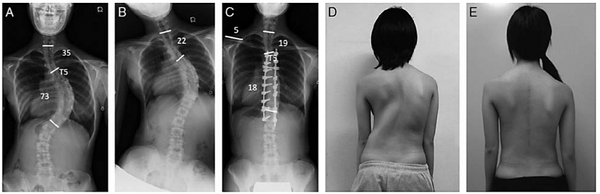

Но это не все, позвонки в зоне деформации (изменение в аксиальной плоскости) сворачиваются своей центральной частью внутрь, а задними элементами наружу (торсия). На картинке ниже справа нормальный позвонок, а слева измененный позвонок, желтая точка – проекция спинного мозга в позвоночном канале.

Из-за торсии происходит скручивание грудной клетки (ребра прикрепляются к позвонкам), появляется реберный горб.

Степень взросления определяется по окостенению тазовых костей по методике, которую описал Joseph Risser. Считается, что 3 степень – самое оптимальное время для операции при наличии показаний. Человек уже не будет активно расти, но позвоночник и спинной мозг достаточно эластичные и смогут без всяких последствий перенести коррекцию даже больших деформаций. Примерный возраст 13-15 лет.

Перед операцией обязательно выполняется рентген. Причем особый. Делаются снимки с захватом всего позвоночника (или всего тела) в двух проекциях спереди и сбоку.

Еще делают снимки с наклонами вбок. Если на этих снимках позвоночник плохо распрямляется при наклоне в сторону дуги, то деформация считается ригидной.

Оценивают идиопатический сколиоз по системе, которую разработал американский хирург Lawrence Lenke. Сейчас это мировой стандарт, она довольно сложна, но ничего лучше пока не придумали.

Классификация Василия Дмитриевича Чаклина (4 степени, которые ставят в поликлиниках) не годится для предоперационного планирования. Посмотрите на картинке ниже насколько отличаются две деформации с одинаковыми градусами кривизны.

Дело в том, что она не предусматривает то, насколько коротко можно зафиксировать сколиоз. А в хирургии деформаций борются за каждый сегмент, который можно сохранить без фиксации. Это крайне важно.